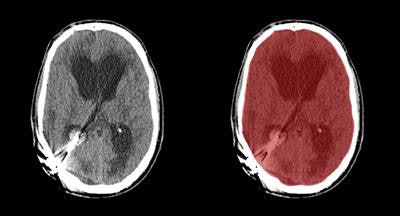

In their study, the researchers developed a way to use software to automatically segment the cranial cavity based on anatomy borrowed from multiple image atlases, then refined the segmentation based on the patient's head CT data. The results closely correlated with manual segmentation of the cranial cavity in CT studies, validating the approach in a database of almost 600 patients.

Prior images in the atlas are registered to the patient image using a two-staged approach, Patel said. The first is an affine registration for a coarse alignment of the images, followed by a second, nonlinear registration to deform the atlas labels to fit the patient image. The method described is used to obtain a segmentation of the entire cranial cavity and does not differentiate between healthy or ischemic regions within the brain parenchyma. The segmentation serves as an initial step in the development of algorithms to detect and quantify anatomical regions and pathology within the cavity.

The automated results were compared with the manual annotations of trained observers, which were used as a reference standard.

The multiatlas registration results showed a high degree of overlap with the reference standard, yielding a mean Dice similarity coefficient of 0.973 ± 0.035, and adding levelset refinement increased the value to 0.984 ± 0.026.

The results encompass a large spectrum of anatomical and pathological variations seen in everyday clinical practice, and they closely approach the high performance of expert manual annotation, the authors wrote.